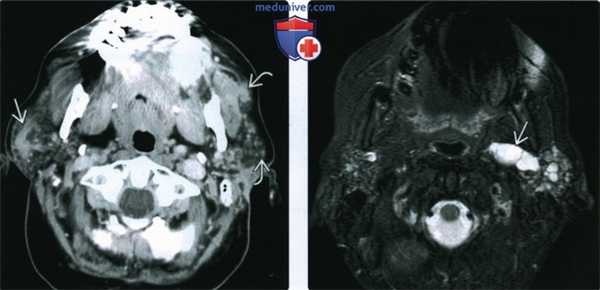

(Слева) КТ с КУ, аксиальная проекция. Диффузная жировая атрофия обеих околоушных желез с участками рубцевания и локального отека. Такая картина характерна для поздних стадий синдрома Шегрена.

(Справа) МРТ Т2ВИ FS, аксиальная проекция. В глубокой доле околоушной железы имеется дольчатое кистозное образование. Так выглядит расширение выводного протока железы при синдроме Шегрена, но здесь его легко можно принять за опухоль.

(Слева) МРТ Т2ВИ FS, аксиальная проекция. Ткань обеих околоушных желез полностью замещена бесчисленными мелкими кистами. Выраженное увеличение размеров обеих желез. Данная картина характерна для острой стадии синдрома Шегрена.

(Справа) КТ без КУ, аксиальная проекция. Тотальная атрофия обеих околоушных желез с замещением их паренхимы жировой тканью. Такая картина характерна для хронической стадии синдрома Шегрена.